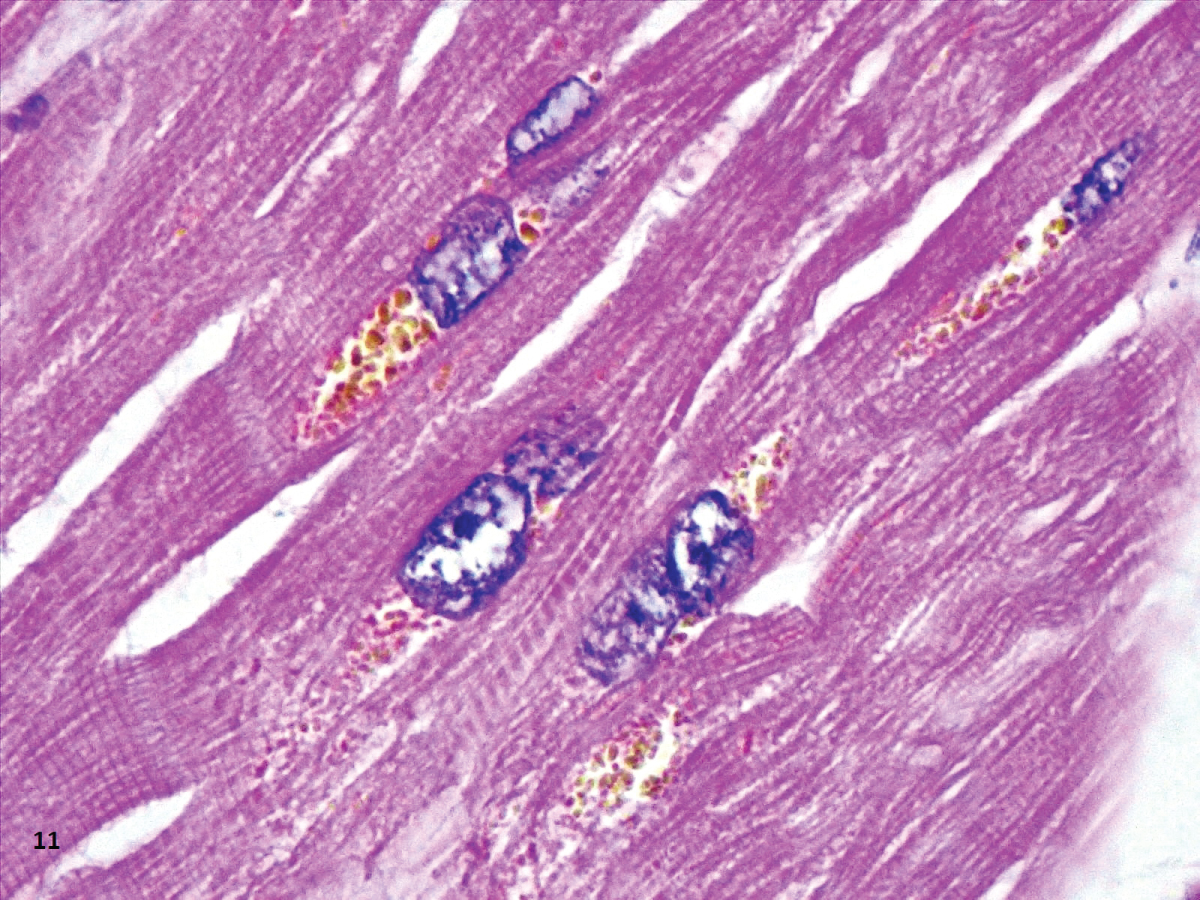

The most common finding in the heart was perinuclear lipofuscin granules inside myocytes. The content of these granules was confirmed with a positive PAS (Periodic Acid-Schiff) and negative Perl’s staining (Figure 1).

The most common finding in heart tissue our heart sample was aggregates of large brown vacuoles filled with lipofuscin, located at the poles of the nuclei in tshe cardiomyocytes (Figure 10 and Figure 11). Deposition of lipofuscin is considered normal as a part of the aging process [39]; however, it calls to our attention that the amounts observed surpass what is expected in aging organs, especially in our six patients younger than 60-years-old. We hypothesize that the origin of these deposits is related to the cardiotoxicity of hydroxychloroquine, as all the patients in our study received cumulative doses from 0.8 to 7.6 g (400 mg/day) of hydroxychloroquine. Our dose is similar to the one used by Lane, et al. who showed an increased risk of heart disease in hydroxychloroquine users [40]. The accumulation of lysosomes with lipofuscin has been previously reported in two patients with cardiac toxicity due to hydroxychloroquine, but the dose was not specified [41].

Figure 11: Section of the heart showing deposits of a paranuclear light-brown material (HE,40X).. View Figure 11

Other findings associated to chronic toxicity of chloroquine (cytoplasmic vacuolization with inclusions of PAS positive granular material), were not identified in our cases. It is important to point out that none of the patients died as a result of cardiac dysfunction. Also, no significant electrocardiographically alterations were observed in any of the patients during hospitalization, even in the patient with myocardial microabcesses.